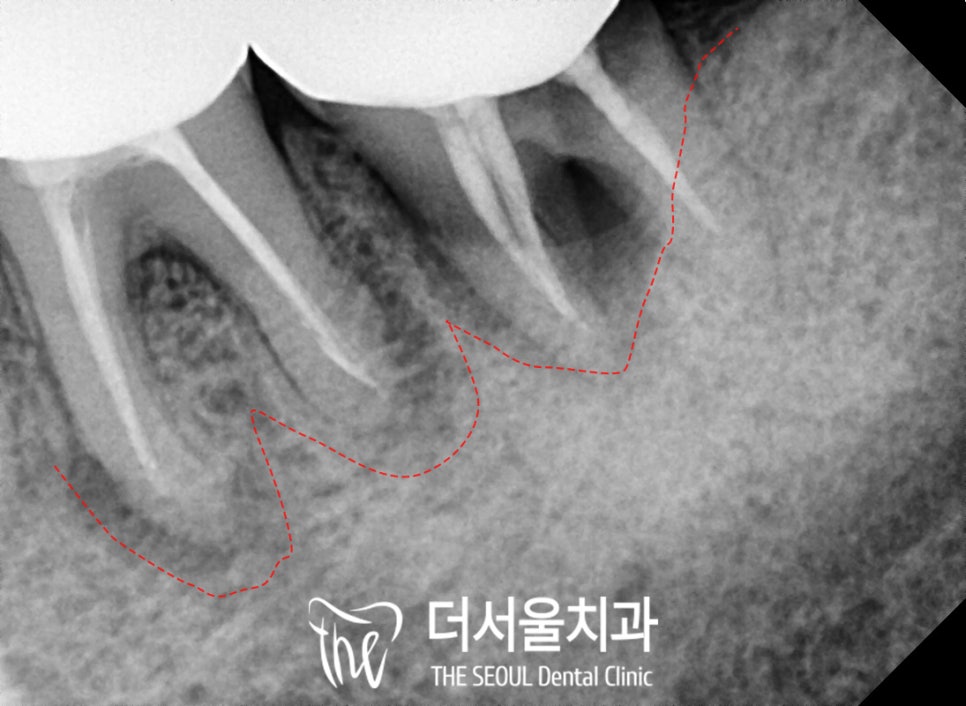

치근단 사진을 통해

더 자세히 살펴보면

이전에 신경치료를 하고

크라운을 씌워두었는데

저작력을 끊임없이 받으면서

크라운 안으로 이차우식이 생기고

치아에 조금씩 파절이 생기면서

주변 치주조직을 모두 녹이고 있었습니다.

그렇기 때문에

boneloss가 나타나면서

잇몸에 까만 방사선 투과성 소견이 보입니다.